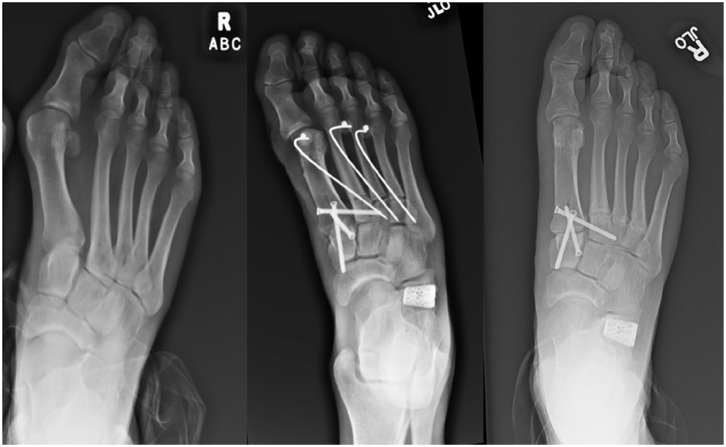

Approaches to Minimally Invasive Surgery for Treatment of Metatarsus Adductus with Hallux Valgus Correction With Modified Lapidus: A Novel Technique Guide.